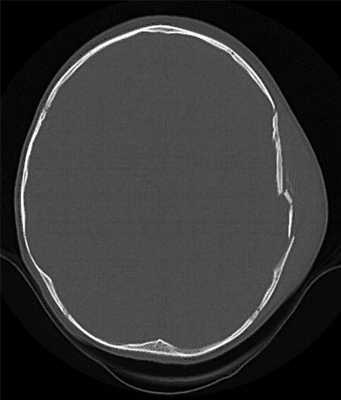

а) Признаки перелома черепа на КТ и МРТ. С помощью компьютерной томографии можно диагностировать три типа перелома черепа: линейные, вдавленные и диастатические. Для визуализации линейных переломов и малых трещин используются алгоритмы реконструкции и фильтры. Переломы черепа могут сопровождаться сопутствующей внутричерепными измененями: гематомами, ушибами, пневмоцефалией или наличием инородных тел, которые могут быть так же выявлены с помощью КТ. Если при переломе имеются раны мягких тканей покровов черепа, то он называется «открытым», так как возникает потенциальная связь между внутричерепным пространством и окружающей средой. В противном случае он называется «закрытым».

Ключевые данные визуализации:

- Заметные переломы не требуют пояснений по диагнозу.

- В остальных случаях на нормальных КТ-срезах возможно появление воздуха внутри черепа (пневмоцефалия) или отсутствие воздуха в обычных областях, например, в околоносовых пазухах, сосцевидных ячейках, среднем ухе или наружном слуховом проходе.

- При отсутствии патологических изменений до травмы возможно жидкостное заполнение пространства СМЖ или кровью, менее плотной по сравнению с СМЖ (метод внутреннего жидкостного наполнения).

- Необходим тщательный поиск субдуральной/ эпидуральной гематомы и ушибов мозга.

- При их наличии определить перелом на тонких срезах с использованием специального костного фильтра/ алгоритма реконструкции.

- При этом перелом будет выглядеть в виде линий на кости без кортикального слоя.

- Необходимо дифференцировать их от обычных швов или другой нормальной анатомической структуры (у которых сохранена кортикальная пластинка, в случае сомнений сравнить с противоположной стороной).